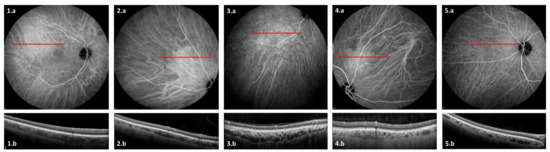

3.3. ICGA Findings

| Vessel leakage and/or staining Hypofluorescent spots Pintpoint leakage Intervortex shunts “Hemangioma-like” lesion | 20 (71%) 19 (68%) 15 (54%) 10 (36%) 5 (18%) |

| OCT anomalies | Number of eyes (%) |

| Pachyvessels Focal choroidal thickening Caverns | 25 (89%) 7 (25%) 6 (21%) |

| 1 | Male | 64 | ARDS with myasthenia decompensation | ND | No | Yes | Yes | No | Yes | Yes | No | No | Yes | Yes | Choroidal folds |

| 2 | Male | 48 | ARDS with DKA and ARF | Moderate | Yes | No | No | No | No | Yes | Yes | No | Yes | No | |

| 3 | Male | 70 | ARDS with PE and HF | Severe | Yes | No | Yes | Yes | No | Yes | Yes | Yes | No | No | Retinal atrophy |

| 4 | Female | 63 | ARDS with DKA | ND | No | No | Yes | No | No | Yes | Yes | No | Yes | Yes | |

| 5 | Male | 65 | ARDS | Severe | Yes | Yes | Yes | No | Yes | Yes | No | Yes | Yes | No | |